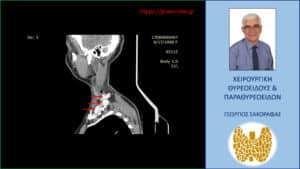

Τα ευρήματα του υπερηχογραφήματος επιβεβαιώθηκαν σε αξονική τομογραφία τραχήλου την οποία προσκομίζει η ασθενής (είχε γίνει πριν το υπερηχογράφημα) (βλ. εικόνες).

Αξονική τομογραφία – διατομή σε προσθιοπίσθιο επίπεδο. Εμφανείς οι ευμεγέθεις λεμφαδενικές μεταστάσεις, κάποιες από τις οποίες επισημαίνονται με τα κόκκινα βέλη.